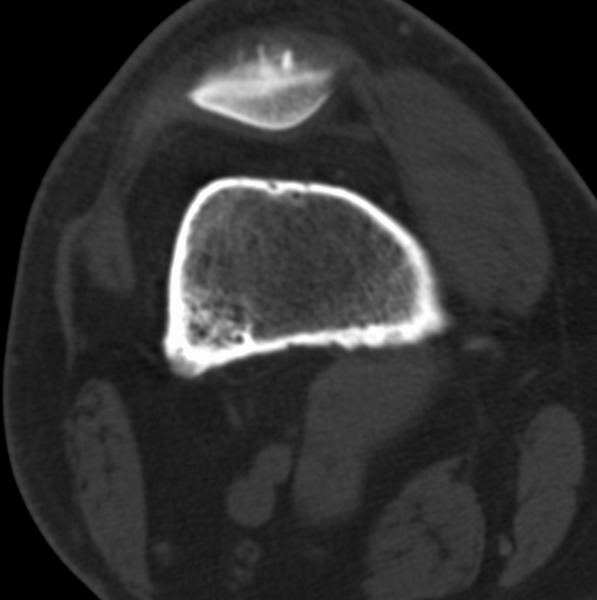

右侧膝关节疼痛一月

男、48

股骨下段、胫骨上段。

股骨干骺端病变考虑非骨化性纤维瘤。

1、股骨干骺端病变考虑干骺端纤维性皮质缺损愈后(非骨化性纤维瘤)改变,胫骨近端内生骨瘤;

2、骨关节炎,骨质增生,股骨外侧髁退变性囊肿(关节面软骨下囊肿);